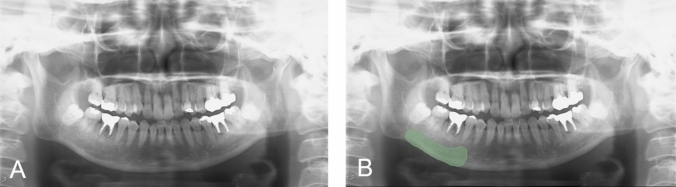

Methods: We included patients who underwent panoramic radiographic evaluation at Hiroshima University Hospital prior to bone resorption inhibitor administration. Thirty-two patients with MRON of the mandible (16 men and 16 women) and 57 without MRONJ (23 men and 34 women) were selected. The mandible was segmented from the mental foramen to the anterior mandibular angle notch on panoramic radiographs before treatment. The image features within this region were extracted and quantified. Overall, 13 shape, 18 histogram-based, 75 texture-based, and 744 wavelet features were extracted. Least absolute shrinkage and selection operator regression were used to select relevant features from the extracted data. Support vector machine (SVM) and neural network of multilayer perceptron (MLP) were used as machine-learning models. The sensitivity, specificity, and area under the curve (AUC) from the receiver operating characteristic curves were used to evaluate diagnostic performances.